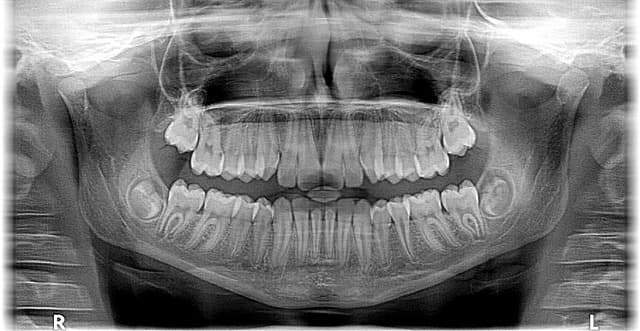

스트레스는 이갈이(브룩시즘)를 유발하는 주요 요인 중 하나로, 이는 어금니 통증의 중요한 원인으로 작용합니다. 스트레스 상황에서는 무의식적으로 이를 꽉 물거나 가는 습관이 나타나며, 이는 어금니 표면의 마모를 가속화하고 치아의 민감도를 높입니다. 이갈이는 치아의 물리적 손상뿐만 아니라 턱관절에도 압력을 가해 어금니 주변의 지속적인 통증을 초래합니다. 이 문제를 해결하기 위해 스트레스 해소법을 실천하고, 맞춤형 마우스 가드를 사용하는 것이 효과적입니다.

스트레스는 턱관절 장애(TMJ)의 주요 촉진 요인으로, 이는 어금니 통증과 깊은 연관이 있습니다. 스트레스를 받을 때 턱관절 주변의 근육 긴장이 과도해지며, 이는 관절의 불균형을 초래합니다. 턱관절 장애는 입을 여닫을 때 통증을 유발하며, 이러한 압박이 어금니로 전달되어 만성적인 통증을 악화시킬 수 있습니다. 초기 증상으로는 턱관절에서의 소음과 불편함이 나타날 수 있으니, 스트레스 관리를 병행하며 치과 치료를 받는 것이 필수적입니다.

스트레스는 면역 체계를 약화시키며, 이는 구강 내 염증성 질환의 발생 위험을 높입니다. 어금니 주변 잇몸에 염증이 발생하면 치아를 지지하는 조직이 약화되어 통증이 발생할 가능성이 커집니다. 특히 치주염은 스트레스와 관련이 깊은 질환으로, 스트레스가 심할수록 염증 반응이 강화되어 어금니 통증을 유발할 수 있습니다. 이와 같은 문제를 예방하려면 철저한 구강 위생과 함께 스트레스를 줄이기 위한 생활습관 개선이 필요합니다.